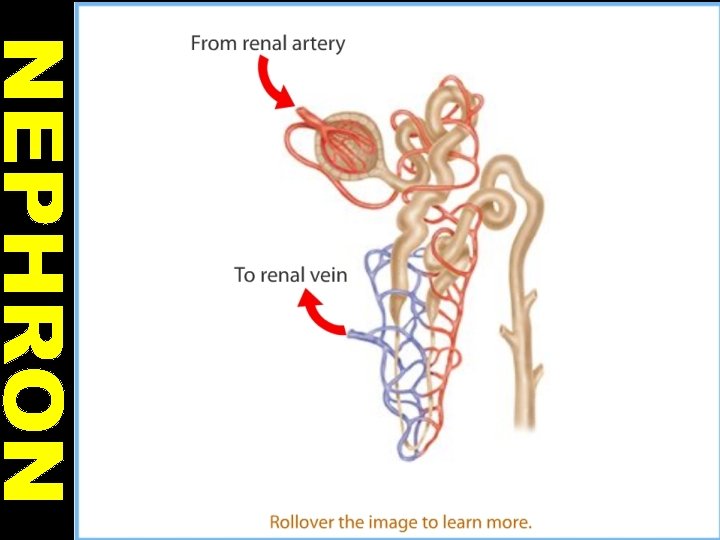

NEPHRONS • They are structural unit of kidneys. • A nephron begins with a glomerulus. • Glomerulus is surrounded by a Bowman’s capsule. • Each glomerulus is formed by capillaries from a branch of renal arteriole.

• The complex of Bowman’s capsule and glomerulus is called malpighian body. Bowman’s capsule is connected with long tubule that is called Loop of Henle. • Loop of Henle is joined with collecting duct.

KIDNEY • Kidneys are bean shaped organs that filtere 180 lt. blood in a day. • Blood is come into kidney by renal artery. • Filtered blood leaves from kidney by renal vein.